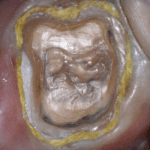

This case was scanned by two different scanners. Once by the Medit i500 and another time with the Aoralscan. Both the meshes are included so you can compare the two. It was scanned to deliver a case that retrofits a partial denture